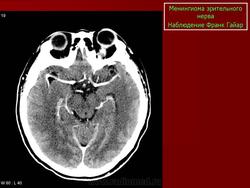

На КТ срезах без контрастного усиления менингиома зрительного нерва выглядит изоденсной. Типично наличие линейных или точечных обызвествлений. Симптом «трамвайных рельс» отражает накопление КВ по сторонам гиподенсного зрительного нерва или наличие обызвествлений в структуре опухоли. Как правило, наиболее дистальная часть зрительного нерва, в месте его вхождения в глазное яблоко, не содержит обызвествлений.

При исследовании необходимо определить расположение бляшковидной менингиомы относительно бугорка турецкого седла и пластинки клиновидной кости, так как данный тип опухоли может распространяться интракраниально через канал зрительного нерва. КТ не позволяет адекватно визуализировать интракраниальное распространение опухоли, которое может привести к развитию двусторонней слепоты.